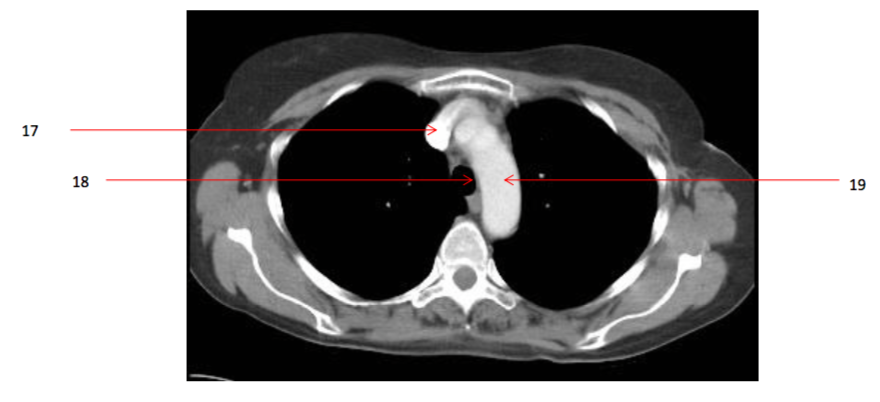

Number 23?

Number 20?

Number 21?

Number 22?

Number 33?

Descending thoracic aorta